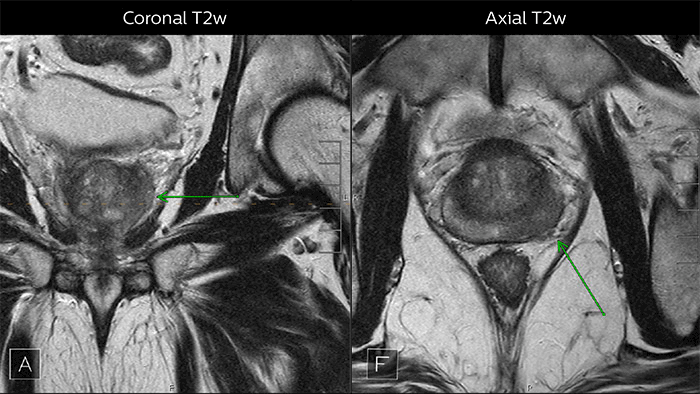

Depending upon the Gleason score and prior therapies, prostate carcinoma has a certain predictable pattern on multiparametric MRI, according to Dr. Steiner. “In general, lesions in the peripheral zone have decreased T2-weighted signal and are relatively focal,” he says. “In the transitional zone, these lesions are more difficult to evaluate on T1 and T2, but are generally non-encapsulated.”

Multiparametric MRI of a classic peripheral zone lesion Dr. Steiner describes this case: “For lesions in the peripheral zone of the prostate, the DWI (diffusion weighted imaging) and ADC map are most helpful for diagnosis. In this case, the DWI shows a very bright signal, which indicates diffusion restriction. The arcuate area with significant signal drop out (arrow) on the ADC map is recognized as highly suspect for tumor. On the axial T2-weighted image the capsule contour looks a little irregular (arrow), which we interpret as capsular disruption, and I usually give a measurement: this lesion shows larger than 1.5 cm capsular disruption. I don’t see any signs of lymphadenopathy, but interpret this lesion as PI-RADS 5. The hypervascular flow pattern in the bottom images adds to the diagnostic confidence.”